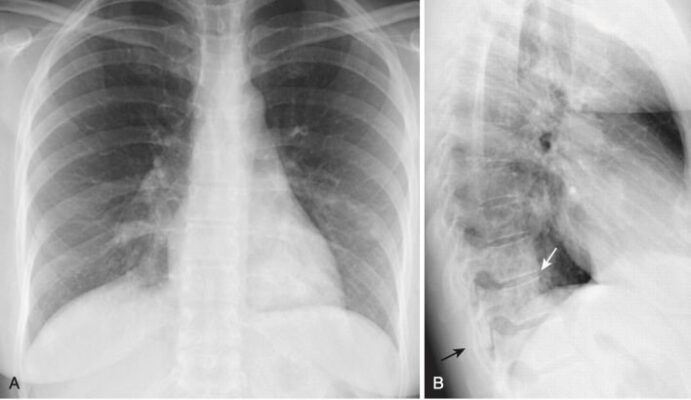

- Nó có thể chứng tỏ bệnh lý không quan sát được trên phim thẳng (Hình 4).

- Rốn phổi có thể khó đánh giá khi nhìn trên phim thẳng, đặc biệt nếu cả hai rốn phổi đều hơi to ra, vì không thể so sánh với bên đối diện bình thường b.

- Xem phim nghiêng có thể hữu ích. Hầu hết các đậm độ ở rốn phổi được tạo thành từ các động mạch phổi. Bình thường, không có khối rõ ràng có thể nhìn thấy trong vùng rốn phổi trên phim chụp X quang nghiêng.

- Khi có một khối ở rốn phổi, chẳng hạn như các hạch lympho to ra, rốn phổi (hoặc cả hai rốn phổi) sẽ tạo ra một bóng mờ hình khối, có thùy, rõ rệt trên phim chụp X quang nghiêng (Hình 7).